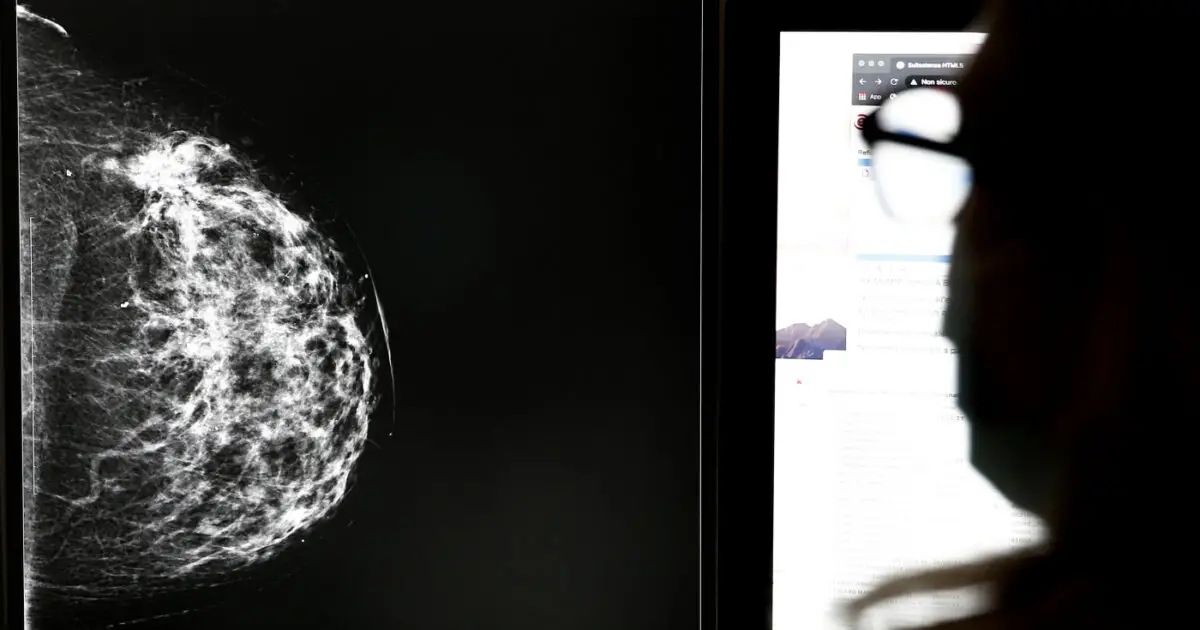

Mammografie “dubbie” ma donne mai ricontattate: lo scandalo degli screening oncologici travolge l’Andalusia

Centinaia, forse migliaia di donne andaluse non sono mai state avvisate dei risultati sospetti delle loro mammografie. Tanto da aver scoperto solo dopo anni di avere un tumore al seno in fase avanzata. Quello che sembrava un errore tecnico si è rivelato un colossale fallimento istituzionale, che oggi travolge la Junta de Andalucía, governata dal […] L'articolo Mammografie “dubbie” ma donne mai ricontattate: lo scandalo degli screening oncologici travolge l’Andalusia proviene da Il Fatto Quotidiano.